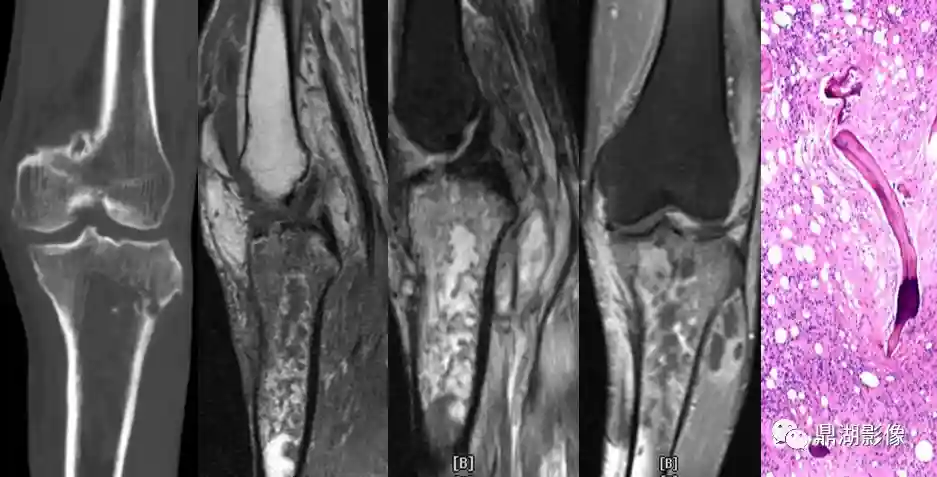

例1:

58Y/M,发热伴左膝关节疼痛半月,病理:炎性坏死,并见局灶小脓肿形成,另见部分骨髓组织,骨髓腔间肉芽组织增生,符合感染性病变